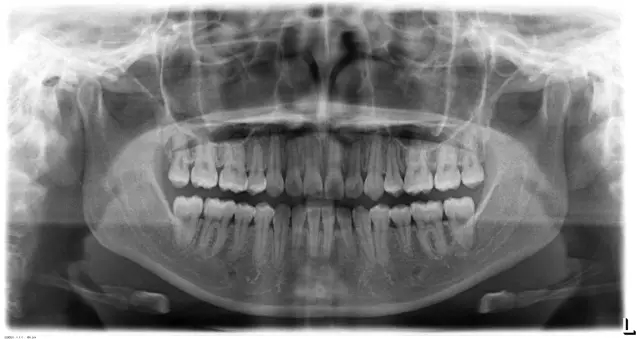

Damon 病例分享:安氏 II 類(lèi)二分類(lèi)露齦笑的矯治(董一磊)

患者信息

治療前后對(duì)比